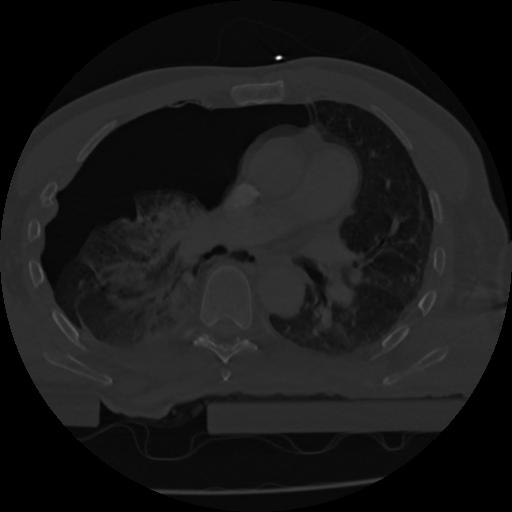

22 ANGIO,CE,Vol,0.5,ANGIO,,